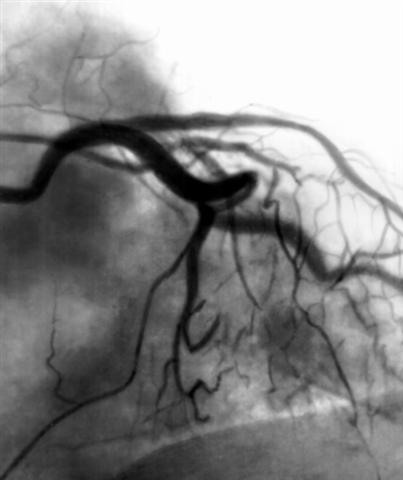

Рис. 1б). Коронарограммы при стенозе передней межжелудочковой ветви левой венечной артерии после рентгеноэндоваскулярной дилатации.